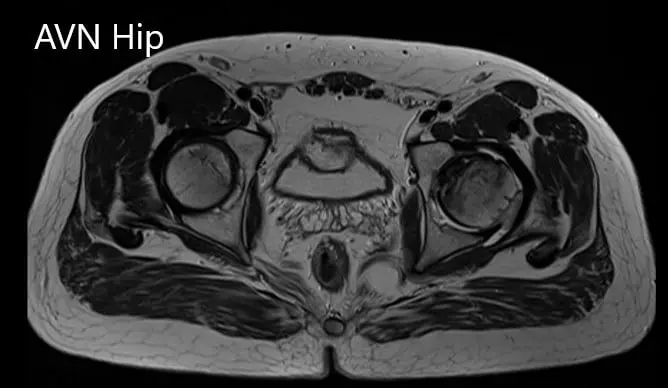

Imaging studies obtained in the form of an X-Ray suggested sclerosis of the left head of the femur. There were marked acetabulum changes. An MRI was further obtained suggesting avascular necrosis of the superior lateral head of the femur with changes in the acetabulum. There was marked hypointense areas on both T1WI and T2WIs.

Axial sections of the T1WI

Axial sections of the T1WI and T2WI of MRI.